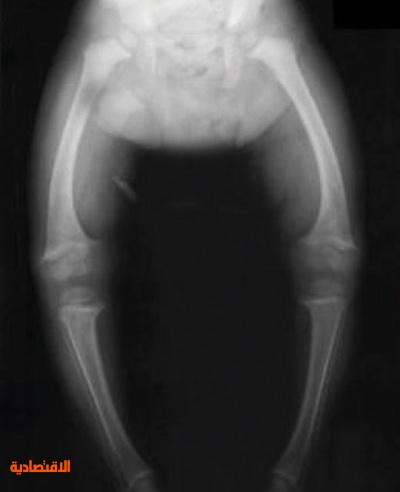

وأشارت الأبحاث إلى أن من أهم الأعراض الدالة على نقص فيتامين (د) عند الأطفال تأثر نمو العظام والأسنان مما يظهر بعض الأعراض من أهمها النمو بصورة غير طبيعية كأن يحدث تقوس ساقي الطفل المصاب أو تشوهات في الجمجمة مثل أن تصبح الجبهة مسطحة. وأضاف الباحثون أن مرض الكساح ينتشر في المناطق السعودية بنسب متفاوتة وبرغم قلة الأبحاث إلا أن مؤشر الإصابة بالمرض ارتفع من 1.4 في المائة وسط الأطفال المنومين في مستشفى السليمانية للأطفال عام 1985 حتى بلغت النسبة 3.1 في المائة عام 1987 في المستشفى ذاته، وفي بحث في مدينة جدة نشر عام 1997 كانت نسبة الأطفال المصابين بنقص الكالسيوم 9.1 في المائة، وفي عام 2009 بلغت النسبة نحو 25 في المائة من الأطفال الذين أجريت عليهم الدراسة في مستشفى الملك فهد في الحرس الوطني. وأكد خبراء التغذية العلاجية أن مخزون فيتامين (د) للرضع يتأثر بمدى تغذية الأم الحامل وصحتها، حيث تزداد احتياجات الحامل للكالسيوم مقارنة بغير الحامل وذلك لحاجة جسمها ولنمو عظام الجنين، إضافة إلى تكوين مخزون من فيتامين (د) للرضيع لحاجته المستقبلية إلى نمو العظام والأسنان، وفي بحث أجري في جدة شمل 264 امرأة حاملا وجد أن أكثر من 9 في المائة منهن يعانين هن ومواليدهن نقص فيتامين (د).